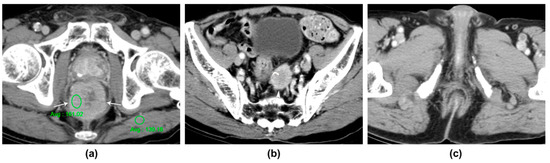

| 67/F | Hematochezia | CT | Ra | Eccentric wall thickening | 14 | Homogeneous | Moderate (1.36) | Yes | 2/12 | Yes | No | No |

| 76/M | Abdominal pain | CT | Ra | Circumferential wall thickening | 14 | Homogeneous | Moderate (1.23) | No | 1/8 | No | No | No |